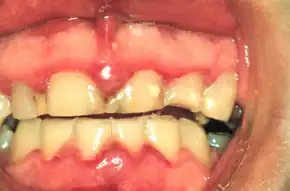

| A fairly mild presentation of acute necrotizing ulcerative gingivitis at the typical site on the gums of the anterior mandibular teeth. | |